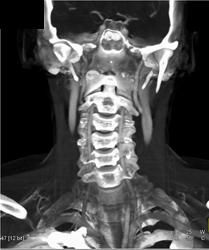

Normal Carotid Artery